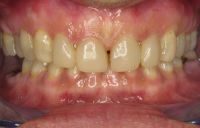

Voor de behandeling

Gebitsslijtage voornamelijk door knarsen. Aan de binnenkant zijn de tanden erg dun geworden en daardoor ook afgebroken. Door de diepe beet zijn de kiezen in onderkaak helemaal afgebroken.

Na de behandeling

De zes voortanden en twee kleine kiezen in de bovenkaak zijn opgebouwd met composiet. Hierdoor zijn ze verlengd en volledig ingepakt met composiet, zodat ze niet meer zo snel kunnen breken.

De afgebroken kies in de onderkaak is verwijderd en in het hiaat zijn twee implantaten geplaatst met kronen.

Uiteindelijk heeft meneer ook een beschermende nightguard gekregen om ervoor te zorgen dat het knarsen geen schade kan geven aan zijn gebit.